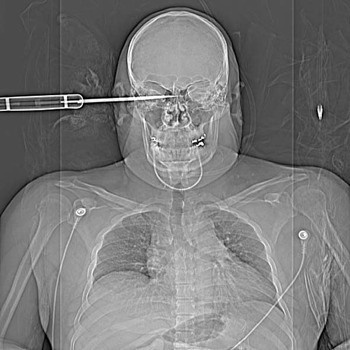

![]() |

| Một binh sĩ Mỹ bị thương trong lúc làm nhiệm vụ ở Iraq. |